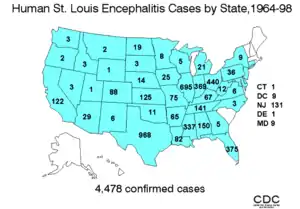

In the United States an average of 128 cases of Saint Louis encephalitis are recorded annually. In temperate areas of the United States, Saint Louis encephalitis cases occur primarily in the late summer or early fall. In the southern United States where the climate is milder Saint Louis encephalitis can occur year-round.